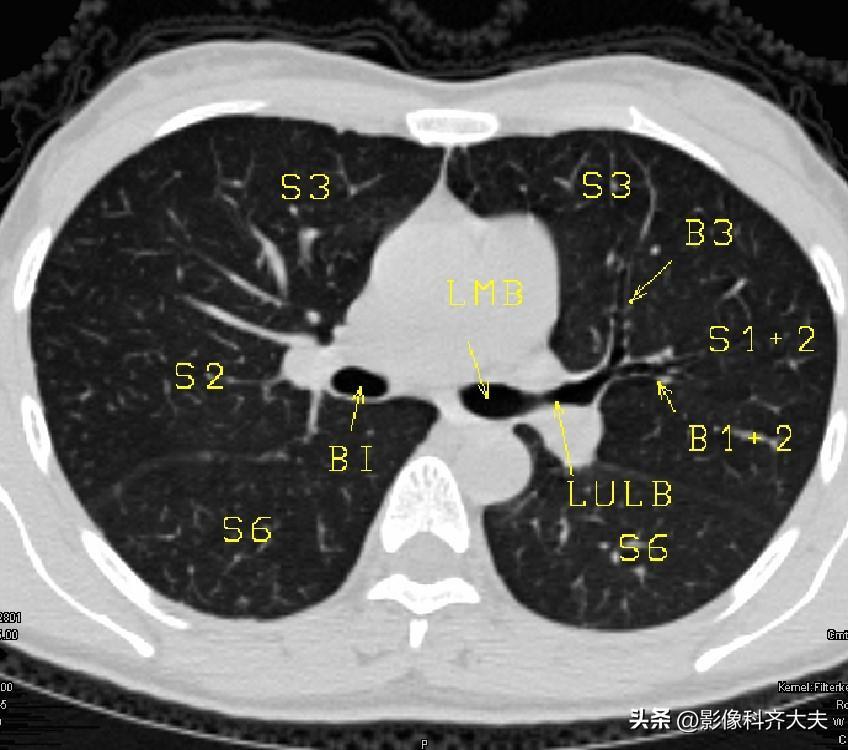

图8-隆突下1cm层面 图8-隆突下1cm层面

▲LUMB:左上叶支气管